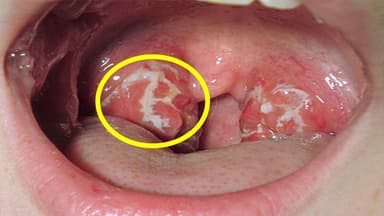

Ung thư hầu họng thường xảy ra ở vùng giữa của họng, bao gồm amidan, gốc lưỡi và thành sau họng. Một tỷ lệ đáng kể các trường hợp ung thư hầu họng hiện nay được xác định có liên quan đến virus HPV (Human Papillomavirus) – một loại virus lây truyền qua đường tình dục, đặc biệt là qua quan hệ tình dục bằng miệng. Virus HPV có thể gây biến đổi tế bào biểu mô tại vùng miệng – họng và dẫn đến hình thành khối u ác tính sau một thời gian tiềm ẩn kéo dài.

Nội soi vùng vòm họng có thể phát hiện các tổn thương bất thường như khối sùi, loét, thâm nhiễm… thường khu trú ở nóc vòm, thành bên hoặc thành sau. Đây là bước quan trọng để phát hiện sớm tổn thương ung thư.